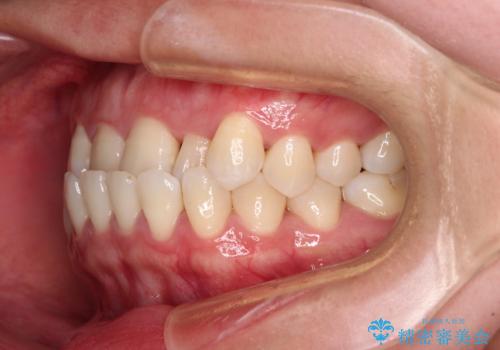

上顎の拡大に伴い反対咬合があっという間に改善されました。

元々の歯列不整は軽微であったため、僅か1年の期間で治療を終えることができました。